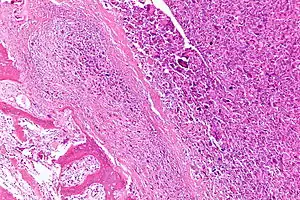

| Intermediate-magnification micrograph of an osteosarcoma (center and right of image) adjacent to non-malignant bone (left-bottom of image): The top-right of the image has poorly differentiated tumor. Osteoid with a high density of malignant cells is seen between the non-malignant bone and poorly differentiated tumor (H&E stain). | |

Microscopically: The characteristic feature of osteosarcoma is presence of osteoid (bone formation) within the tumor. Tumor cells are very pleomorphic (anaplastic), some are giant, numerous atypical mitoses. These cells produce osteoid describing irregular trabeculae (amorphous, eosinophilic/pink) with or without central calcification (hematoxylinophilic/blue, granular)—tumor bone. Tumor cells are included in the osteoid matrix. Depending on the features of the tumor cells present (whether they resemble bone cells, cartilage cells, or fibroblast cells), the tumor can be subclassified. Osteosarcomas may exhibit multinucleated osteoclast-like giant cells.[22]